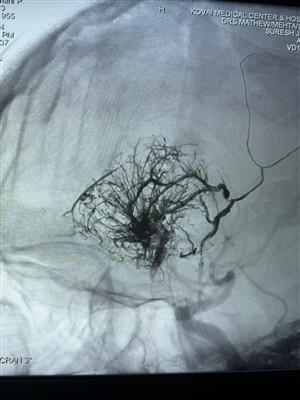

Neues AVM -Gehäuse verwendete Lava -FlüssigkeitsemittelTeilen Sie einen neuen AVM -Fall mit Lava Flüssigempfindlichkeit von Neurosafe Medical Co., Ltd. Das Bild lautet wie folgt:

Mehr -